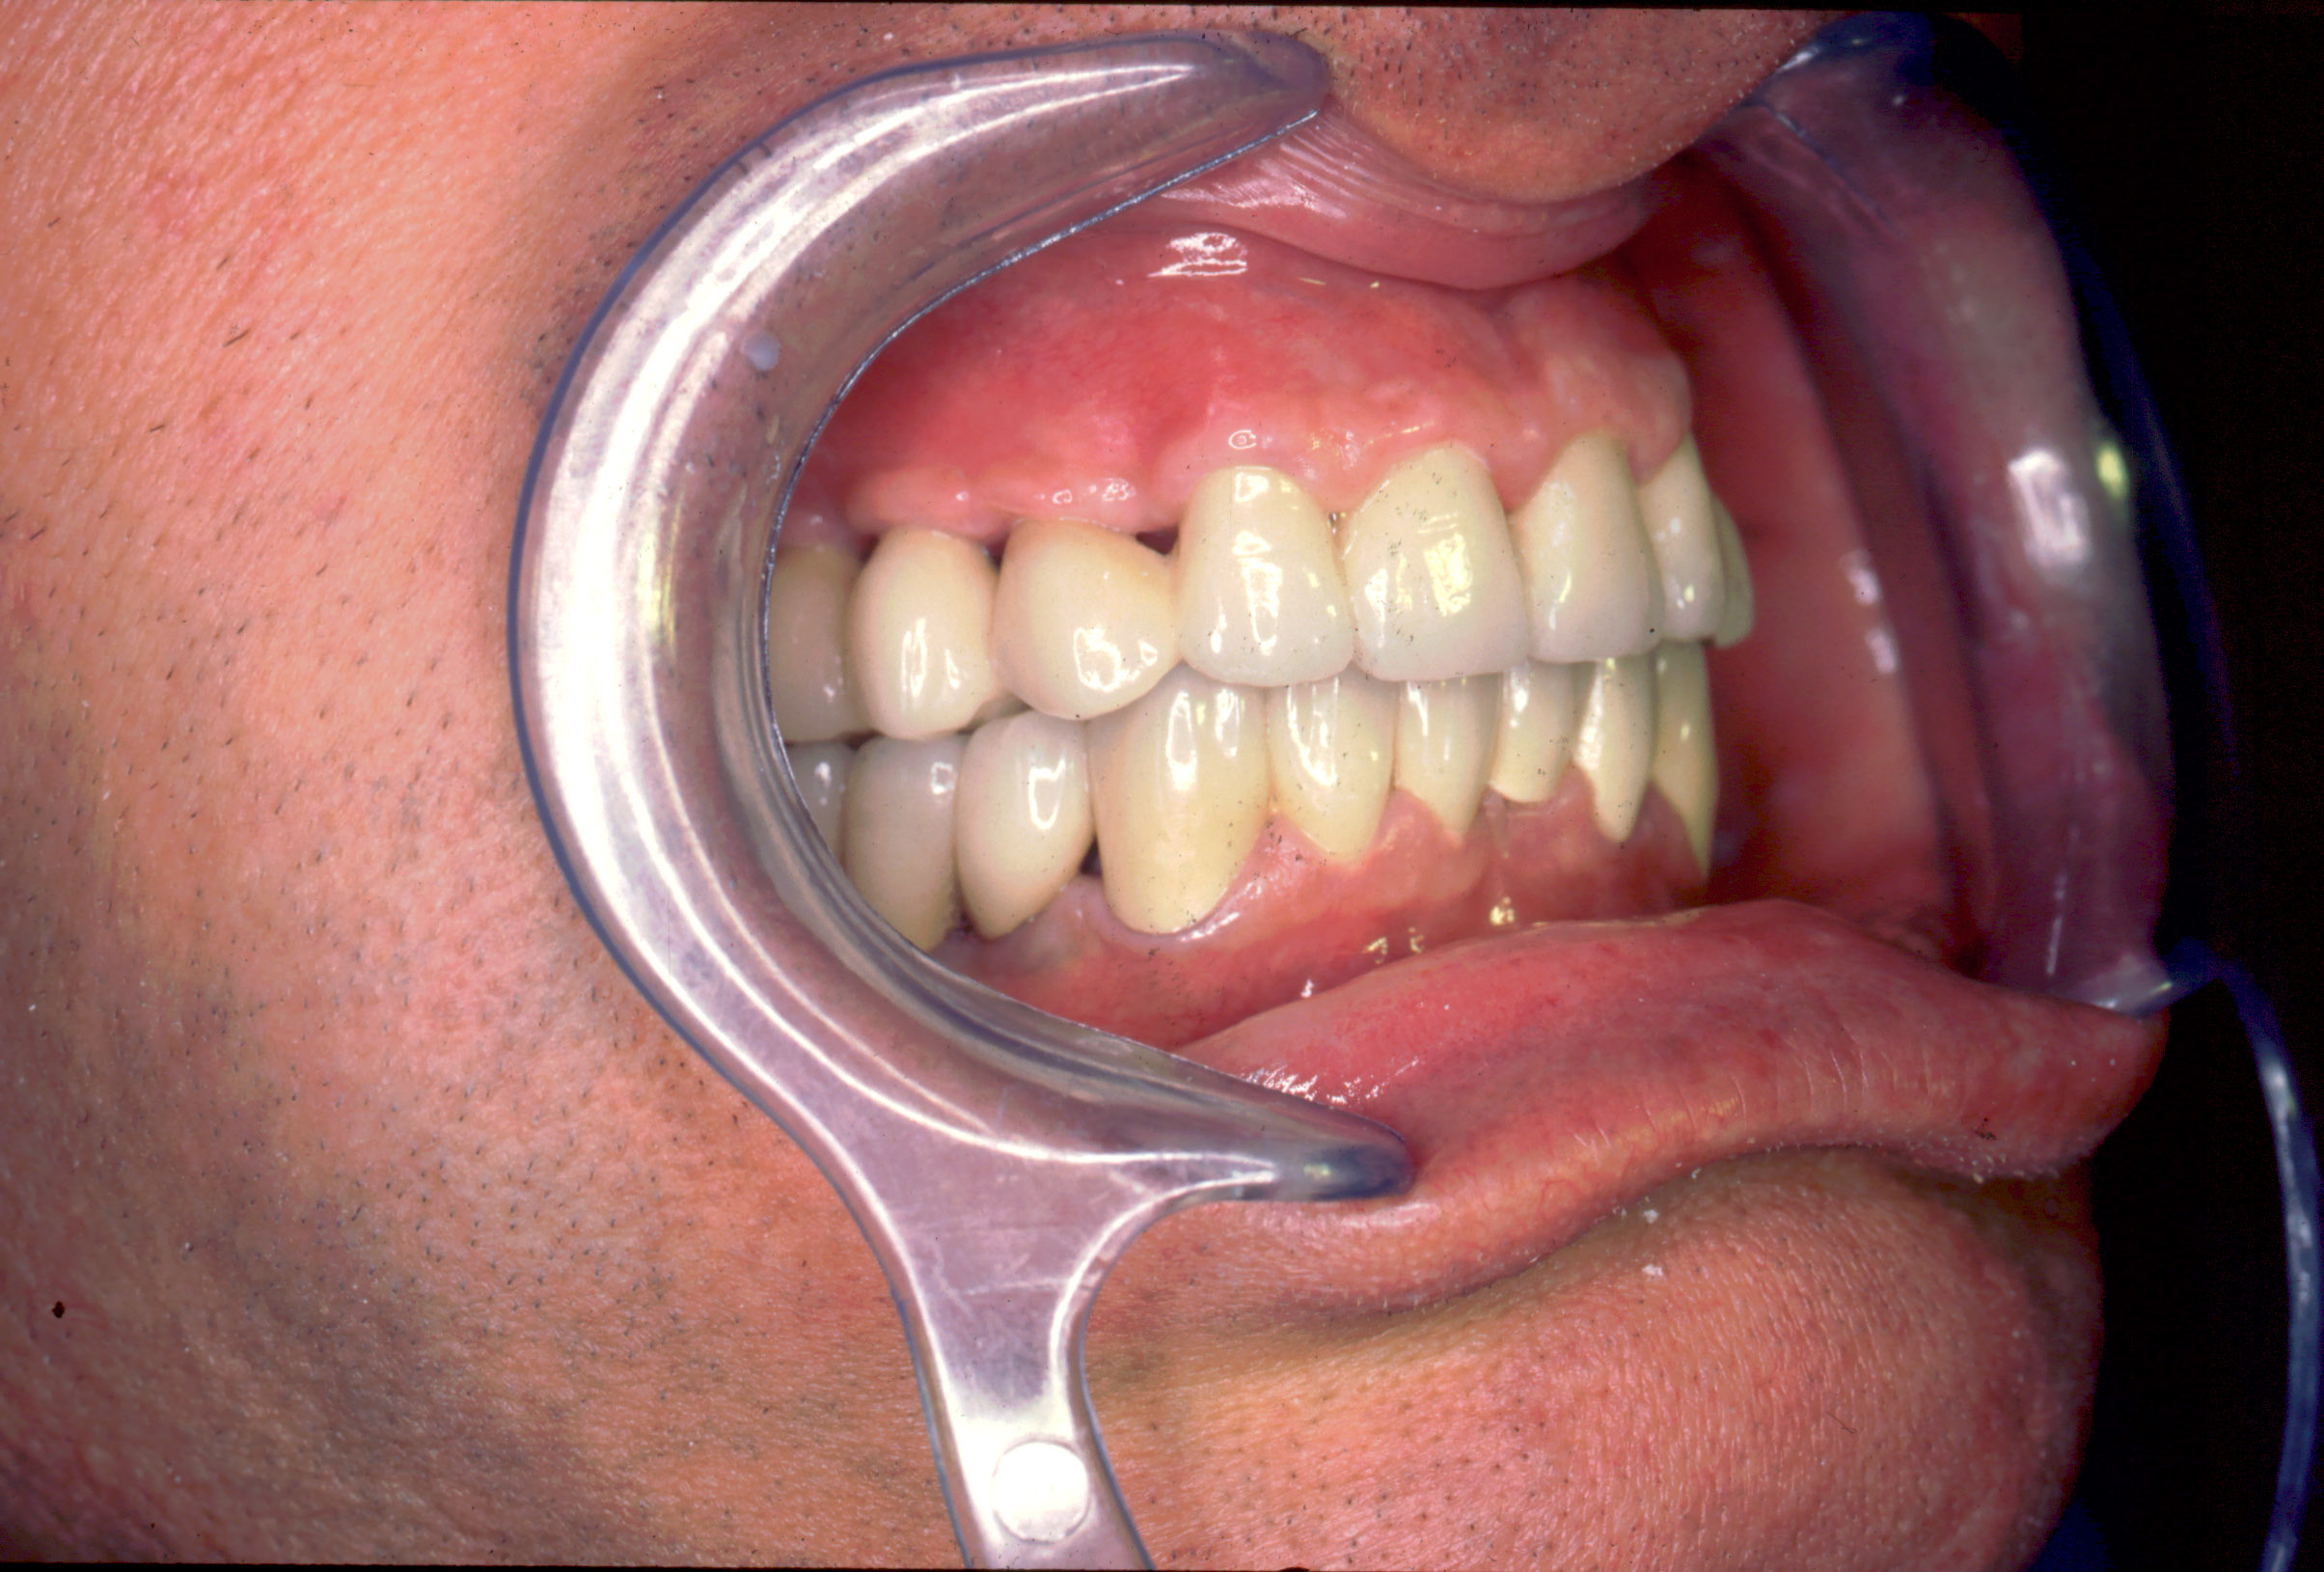

El paciente fue tratado en el año 1994 con una rehabilitación oral. Se instalaron 10 implantes métrica de rosca de conexión 2,3mm : 6 en maxilar superior y 4 en maxilar inferior. En maxilar superior se instalan 3 en segmento distal derecho y 3 en segmento distal izquierdo y permanecen 4 dientes incisivos anteriores superiores como remanente. Con estos 10 apoyos en maxilar superior (3 implantes +4 dientes+3 implantes) se instala una arcada ceramo–metálica superior por segmentos (3+4+3). En mandíbula se instalan 4 implantes en zona distal inferior derecha y una prótesis ceramo–metálica en segmento individual sobre estos 4 implantes, el resto son dientes naturales con coronas ceramo–metálica. Todos los aditamentos utilizados fueron rectos macizos originales de la marca utilizada en aquel momento (titanio grado 3). Así de este modo se realiza la rehabilitación oral.

Actualmente vuelve el paciente de nuevo con la misma prótesis. Había roto dos de los tres pilares en concreto los más distales. El primero de los dos había roto la rosca del aditamento dentro del implante como ocurre habitualmente. Pero el ultimo pilar había roto directamente la cabeza del implante tal como se ve en la radiografía y lo que quedaba era un cilindro de titanio macizo perfectamente integrado en el maxilar, sin posibilidad de enroscar nada. Le explicamos al paciente que habría que quitar y poner un implante en el mismo acto. El paciente dijo que no, así que decimos que no se haría cirugía. Buscamos solución alternativa: hacemos un un agujero en el centro del macizo cilíndrico del implante roto y pasamos sucesivamente el set de machos roscantes. Utilizamos una fresa cañón de 1 mm que poco a poco se va introduciendo hasta 8mm con un poco de vagación, que hace que sea un poco mas de 1mm de diámetro. Posteriormente pasamos el conjunto de machos roscantes de métrica 2mm para poder usar un aditamento experimental, que era un palo de rosca de diámetro 2 mm unido a un cuerpo metálico en forma de sombrero napoleónico fabricado en cromo/cobalto, prototipos primitivos de la sistemática ASATIM y que tienen la característica de tener gran resistencia a la fractura. Nos llevó un tiempo largo el tallado de dichos aditamentos, tal como se puede observar en las imágenes, y tras cicatrizar la encía se le hizo una prótesis estándar. Esperemos que no lo rompa más veces.